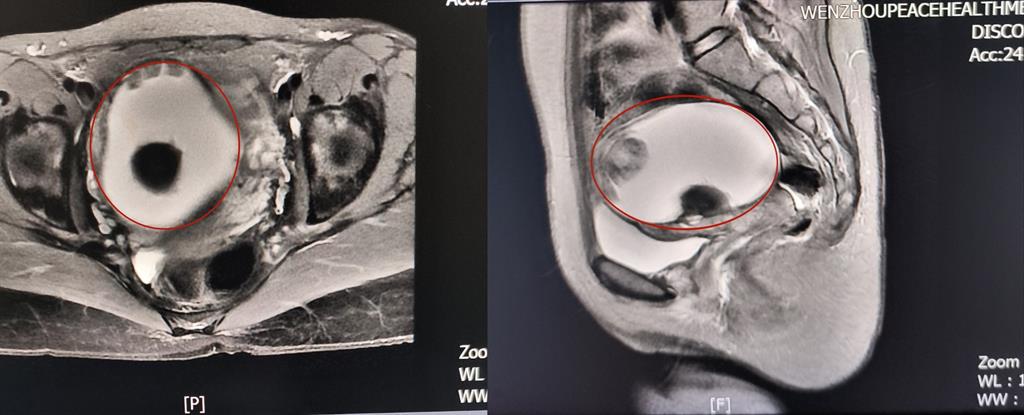

前不久,溫州某高校外籍教師A女士來(lái)到和平國(guó)際醫(yī)院體檢與健康管理中心進(jìn)行深度體檢。B超提示“子宮右側(cè)附件區(qū)囊性塊,大小約82*79*88mm”和平國(guó)際醫(yī)院婦科主任醫(yī)師方軼萍發(fā)現(xiàn),A女士還有三項(xiàng)腫瘤標(biāo)志物數(shù)據(jù)超標(biāo)(甚至高出正常值兩倍)。

卵巢腫瘤?為進(jìn)一步明確診斷,A女士在方主任建議下做了增強(qiáng)磁共振,影像結(jié)果提示:盆腔右側(cè)團(tuán)塊狀占位伴多發(fā)成熟脂肪成分大小約89*100*71mm,考慮畸胎瘤可能性大。謎團(tuán)逐漸解開(kāi),原來(lái)那個(gè)“怪胎”可能是畸胎瘤在作祟。

回家考慮后,A女士決定來(lái)和平國(guó)際醫(yī)院手術(shù)治療。“畸胎瘤大部分是良性,而且患者未婚未育,評(píng)估后我們決定采用微創(chuàng)的治療方案——腹腔鏡下畸胎瘤剝除術(shù)。”方主任講到,這樣不僅創(chuàng)傷小,還能保護(hù)患者的生育能力。

因腫物與周?chē)M織粘連致密暴露困難,這極考驗(yàn)主刀醫(yī)生的經(jīng)驗(yàn)和專業(yè)技術(shù)。為避免腫瘤破裂及血管損傷,和平國(guó)際醫(yī)院婦科團(tuán)隊(duì)主任醫(yī)師方軼萍、副主任醫(yī)師周婷在腹腔鏡下精細(xì)操作,完整切除囊腫,術(shù)中快速冰凍病理檢查結(jié)果證實(shí):成熟型囊性畸胎瘤(良性)。